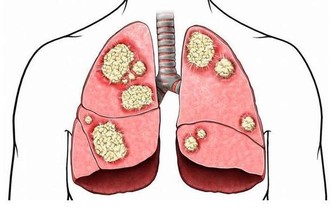

4. 呼吸短促

如果心臟和肺部由於血栓而受到壓迫,則可能會出現呼吸短促。如果同時還有上述關於血栓的其他症狀出現,說明事態比較緊急,必須立即解決。現在馬上看醫生,還有機會恢復健康。

5. 胸痛

當血栓到達肺部時,人們就會在胸部和身體兩側產生劇烈疼痛。這種疼痛非常劇烈,而且有灼燒感,身體這塊區域都很痛苦,感覺很沉重。

6. 運動時疼痛

如果輕輕一動就會感覺疼,那就是血栓的另一個早期預警信號。一個人從正常行為如彎腰、笑或咳嗽中感到不適,表明血栓有可能到達肺部,必須迅速治療。情況嚴重時,還要掛急診。7.原因不明的咳嗽

不明原因並且日漸加劇的咳嗽,也可能是血栓的跡象,表明血栓雖然較小,但已經在肺部形成。更嚴重的跡象包括咳血或產生含有血液的粘液。